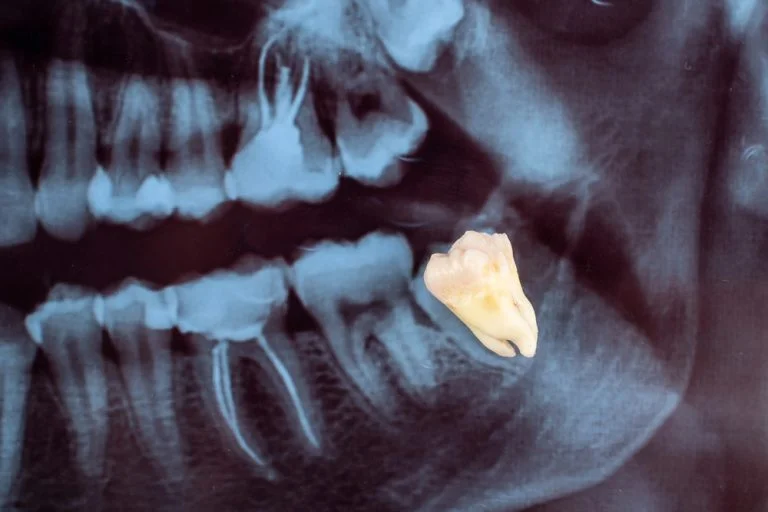

La cirugía guiada en implantes dentales es una técnica en la que todo el tratamiento se diseña previamente en 3D. A partir del TAC dental (CBCT) y del escaneado intraoral, creamos un modelo digital de tu boca para decidir con precisión dónde y cómo colocar cada implante.

Con estos datos fabricamos una férula quirúrgica personalizada que guía la posición del implante durante la cirugía. El resultado es una intervención más predecible, mínimamente invasiva y con una integración más controlada en el hueso.